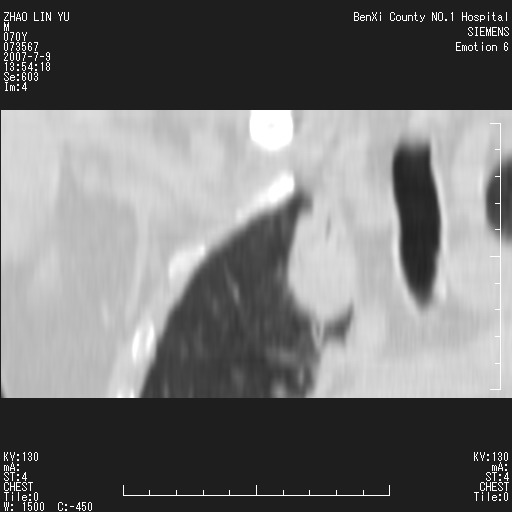

以下是引用王靖旗在2007-7-10 17:12:00的发言:[br] 男、70、咳嗽两个月,半年前换瓣手术,胸片未见异常,于昨天行x片发现右肺上野大片影,行ct扫描,这里是减薄图像,余肺正常。明天晚上会有增强扫描片,到时我会上传。[br][br] 冠状位请大家细看,应该是有意义的,[br][br] 请大家先看平扫发表意见。[br][br]

[br]冠状面[br]

以下是引用zhangzhongshou在2007-7-10 21:43:00的发言:[br]右肺上叶周围型肺癌,以孤立型细支气管肺泡癌可能性大。